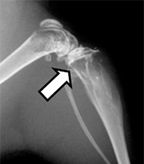

Representative x-ray image from hindlimbs of mouse, arrow indicates osteolytic lesion; source: Dunn LK et al.

PLoS ONE

2009:e6896